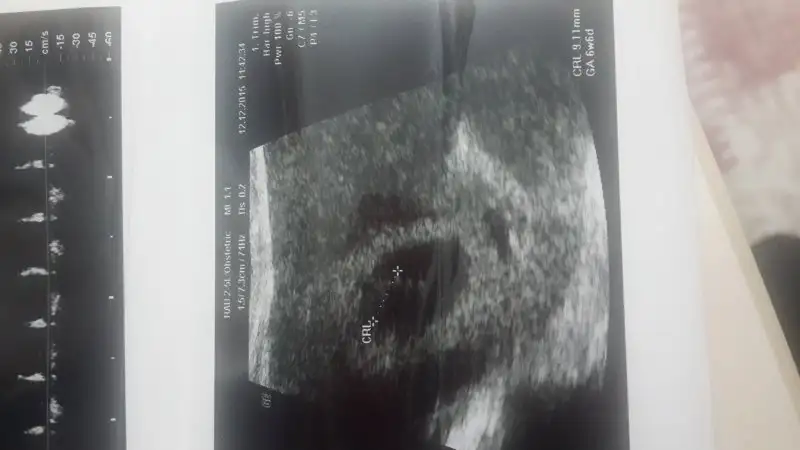

Ulturasondan anliyorsan benim bebegimede bakarmsn 8+4 :)) Eki Görüntüle 1714744 Eki Görüntüle 1714744 Eki Görüntüle 1714750

Arkadaslar benim minnak a da bakın 7 haftalık ultrason